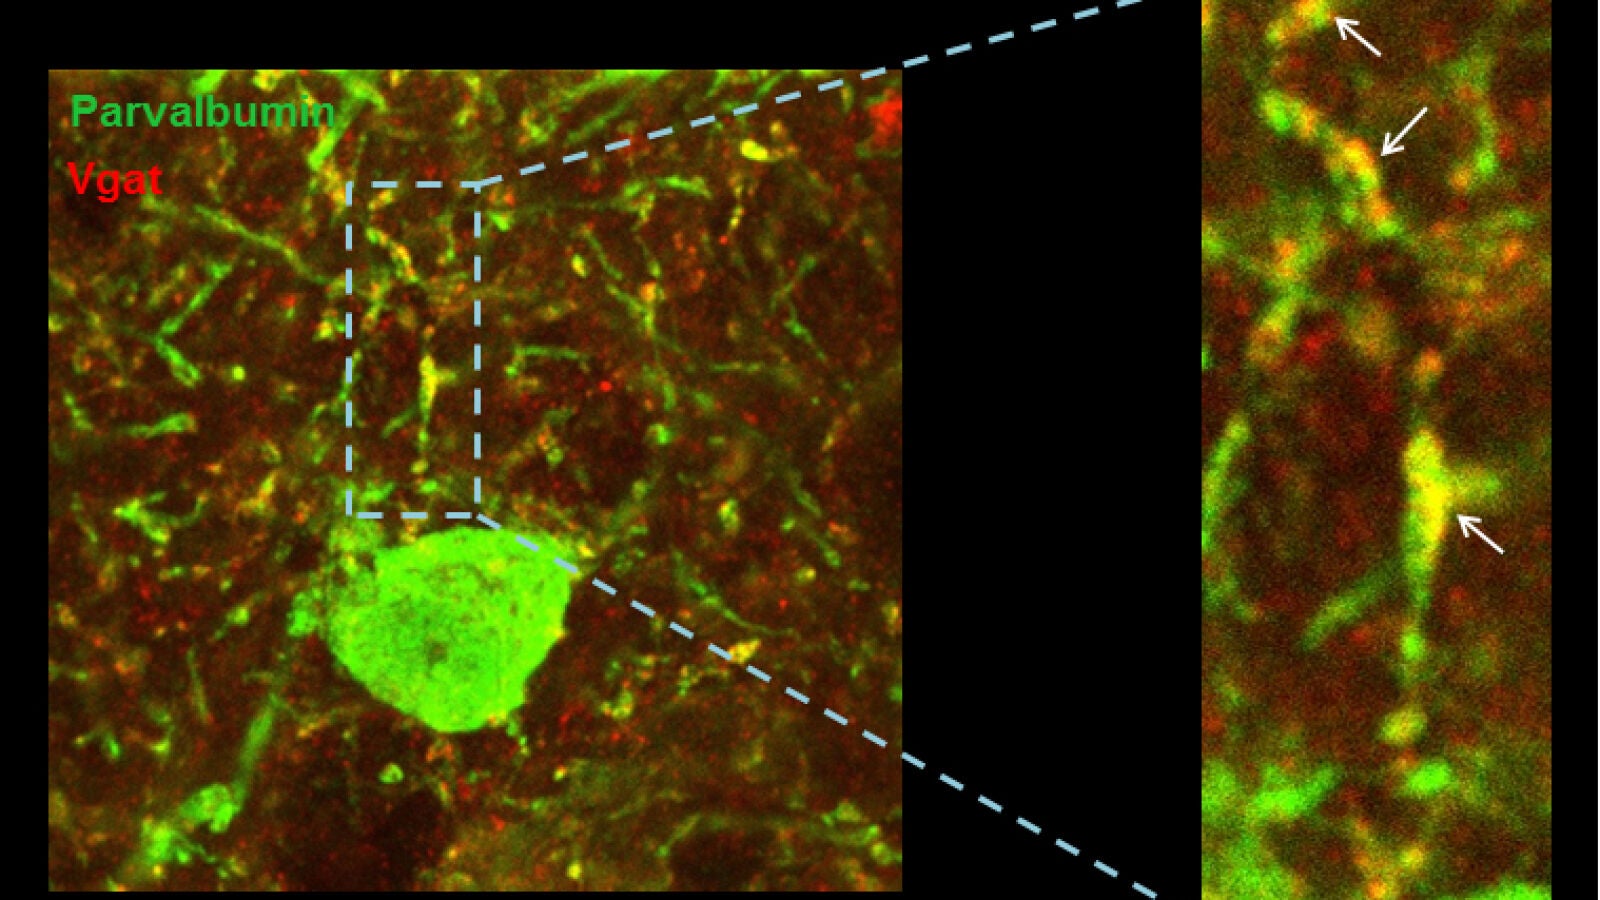

Las científicas se han centrado en uno de los genes relacionados con el síndrome de Down. Mediante experimentos con modelos animales que sobreexpresan el gen candidato, demostraron que el exceso de este gen provoca cambios muy sutiles en el equilibrio excitación/inhibición y estos llevan a una reducción notable de la actividad y sincronización de las neuronas excitadoras en la corteza prefrontal.

Es decir, que cuando este gen se encuentra sobreexpresado, reduce el nivel de descarga de las neuronas y altera el ritmo en las ondas de alta frecuencia de la corteza cerebral. Es más, observaron que el problema radica en unas neuronas que se encargan de controlar la inhibición. En resumen, si hay menos actividad y existe una desequilibrio en las frecuencias de las ondas cerebrales en síndrome de Down es debido a cambios en la conectividad de las neuronas que deben controlarlas.

El estudio ha combinado experimentos de electrofisiología e histología con un modelo computacional que emula el circuito neuronal de la corteza cerebral de forma virtual. “Hemos identificado alteraciones anatómicas y funcionales, y a través de un modelo computacional hemos demostrado cómo dichos déficits pueden explicar las observaciones experimentales” comenta Sánchez Vives, jefe del equipo de Neurociencia de Sistemas y coinvestigadora principal del estudio.